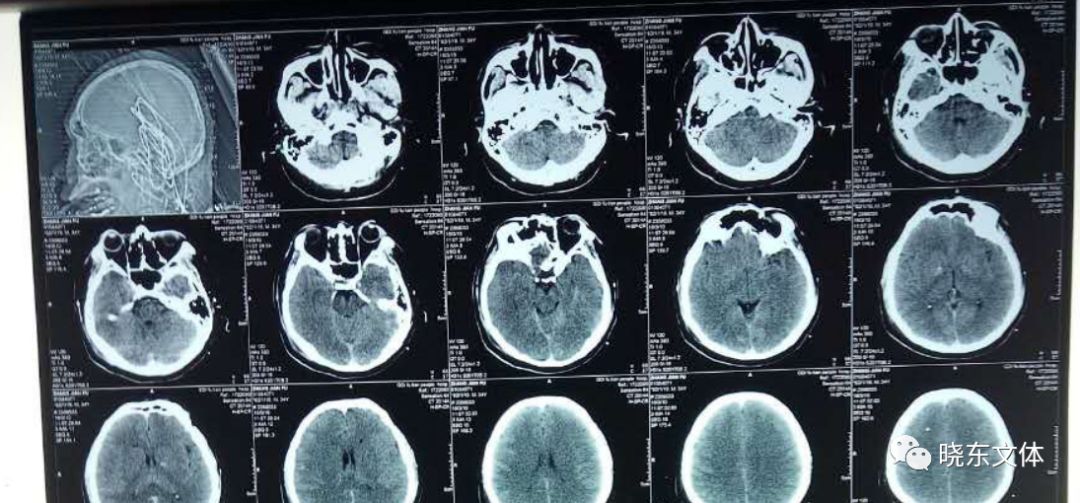

我院ECMO核心小组为患者建立VA-ECMO

入院后,救治小组立即有条不紊地展开各项抢救和治疗。患者长时间缺血缺氧导致多脏器功能衰竭,出现心脏、呼吸、循环、肾脏、肝脏等多器官衰竭,合并严重凝血功能障碍、缺氧性脑病,严重酸中毒、高钾,重度全身水肿。急诊医护团队给予了患者包括ECMO呼吸循环支持、床旁血液透析、呼吸机辅助通气等生命支持以及对症支持治疗。

患者成功运送至我院急诊医学中心ICU病房

患者各项身体指标显示多脏器功能衰竭